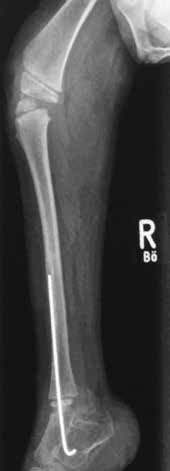

Pränatal wird bei der Patientin im Ultraschall eine beidseitige Fehlbildung der unteren Extremität diagnostiziert. Die Patientin kommt per Sectio in der 31. SSW als Frühgeborenes (Abb. 4a) zur Welt. Das Krankheitsbild präsentiert sich nach der Geburt als beidseitige Tibiaaplasie, rechts Grad 1, links Grad 2a (Abb. 4b). Rechtsseitig besteht eine Kniebeugekontraktur von 110°. Die Patellaaplasie zieht einen fehlenden Muskelstreckapparat nach sich, der Fuß steht in Inversion und Klumpfußstellung, die Großzehe ist hypoplastisch. Linksseitig ist das Kniegelenk frei beweglich. Patella und Streckapparat sind vorhanden, ein Tibiaplateau ist erkennund tastbar. Der linke Fuß steht ebenfalls in Inversions- und Klumpfußstellung. Ein Herzfehler und das sehr niedrige Geburtsgewicht machen zunächst einen mehrwöchigen stationären Aufenthalt notwendig.

- Im Oktober 2009 erfolgt die Erstvorstellung im Universitätsklinikum Münster, im März 2010 die operative Distraktion, Redression und Rekonstruktion der Deformitäten mit externen Fixateuren (Abb. 5a). Die Fixateure werden über ein halbes Jahr in zwei Phasen à drei Monaten mit täglichem Redressment angepasst.

- Der rechte Fixateur distrahiert und fixiert Oberschenkel, Unterschenkel und Fuß. Linksseitig wird nur der Unterschenkel zum Fuß in Stellung gebracht.